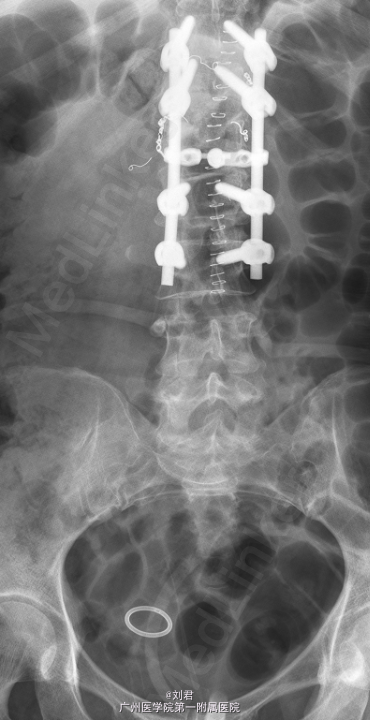

初步诊断:腰椎肿瘤. 手术指征明确,行腹主动脉造影+腰椎动脉超选造影+胸12、腰1、2动脉栓塞术,后行腰椎肿瘤后路肿瘤切除、椎管减压、内固定术。

术后病理:(腰1椎体)血管瘤。术后予抗感染、止痛等治疗。患者术后恢复可,复查腰椎X片示内固定位置可.